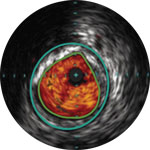

Treatment plan example 2

Lumen with fresh thrombus

Micro-calcification

Calcified plaque with acoustic shadowing

Vessel size: 6 mm diameter Plaque morphology: Mixed, thrombic plaque with medial calcium Plaque geometry: Eccentric lesion Guidewire position: True lumen

Quick-Cross catheter: Confidently cross challenging morphologies Turbo-Power laser atherectomy: Forward facing directional debulking to clear thrombus; rotation for improved deliverability in calcified lesions AngioSculpt scoring balloon: Safely dilate residual stenosis4 Stellarex DCB: Designed for performance in calcium